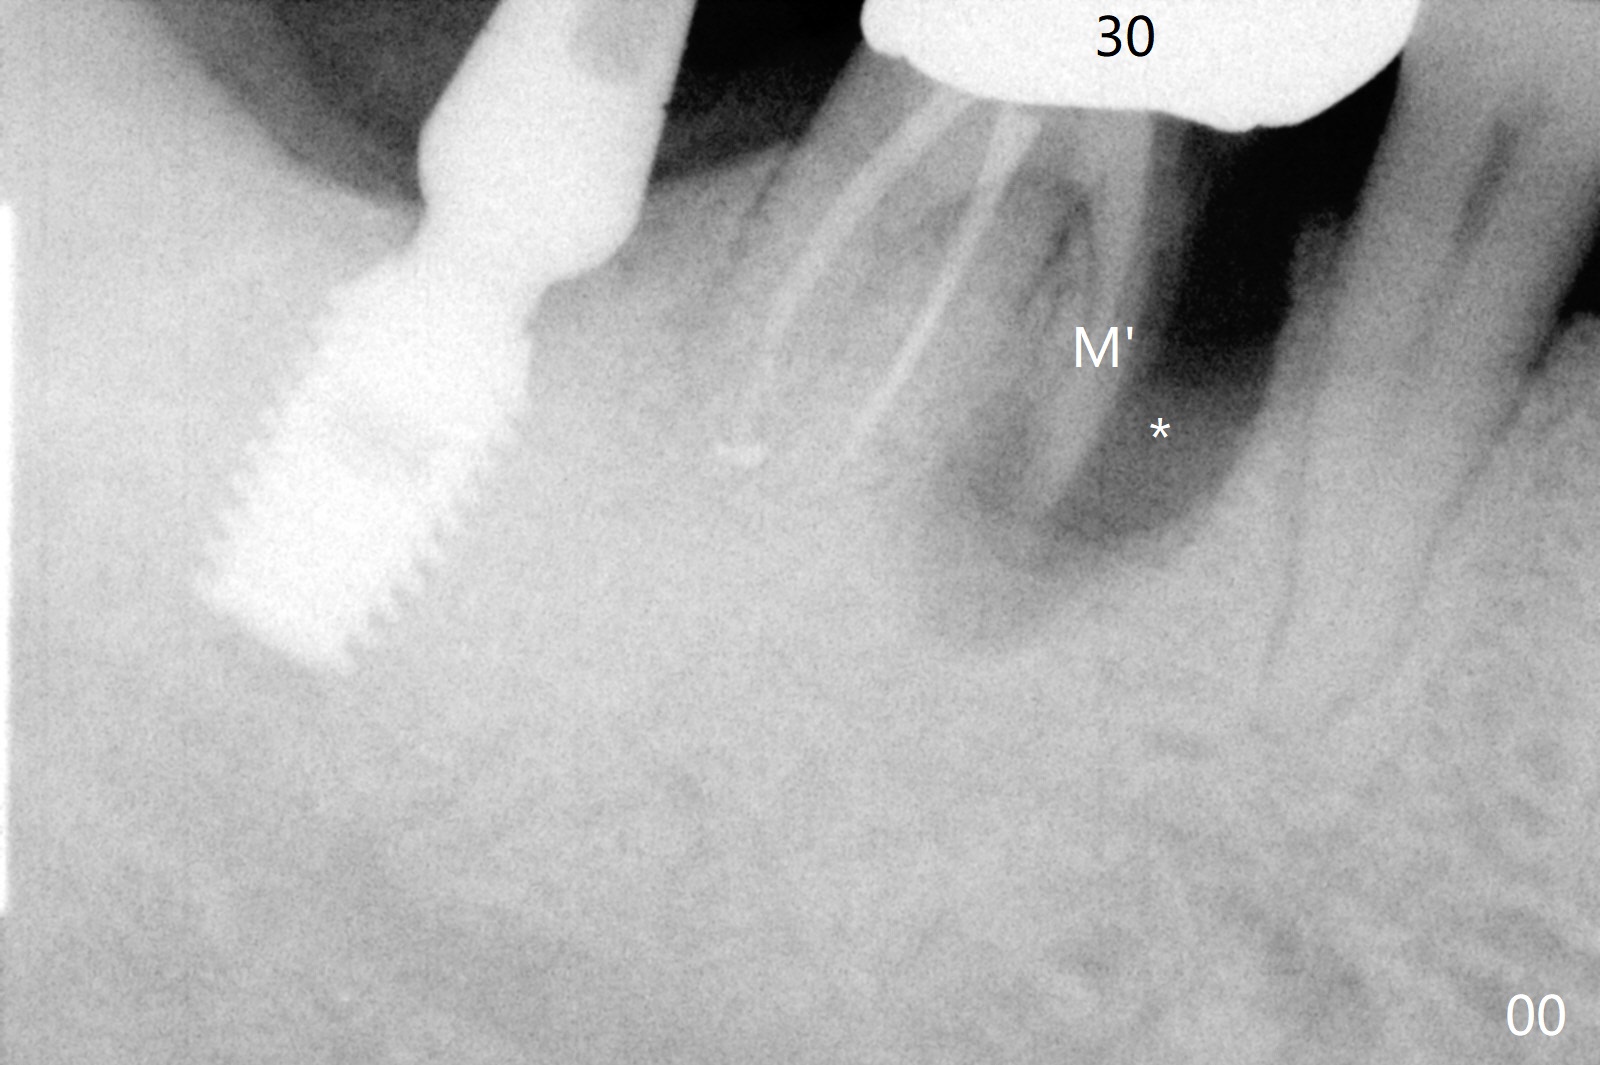

Vertical fracture of the mesial root of the tooth #30 after RCT is associated with bone loss (Fig.00 *). When the mesial portion of the mesial root (M', loose one) is exfoliated, the bone loss resolves (Fig.0). To reduce heat-induced bone necrosis at #19, osteotomy is conducted slowly with copious irrigation with cold saline. Bone density is felt while a 5x10 mm implant is being placed after using cortical tap to the 2nd line of the implant driver. The implant needs to be reverse torqued several times before reaching its final depth (Fig.1 (~50 Ncm)). Since the residual roots are superficially positioned, the immediate implant looks as a delayed one. Although the implant is placed mesial to the septum clinically, its position in X-ray seems to be normal. Because of severe wear and lack of vertical height, a 6.8x5 mm healing abutment is placed. Retention of bone graft (Fig.1 *) is maintained by spreading setting acrylic into the edentulous undercut areas (Fig.2 *). The so called "acrylic dressing" remains in place 3 weeks postop (Fig.8). When it is removed with the healing abutment, the wound heals (Fig.3). Note the limited vertical height. The bone graft placed in the distal socket appears to have been converted to the native bone 3.5 months postop (Fig.4). To reduce severe wear of the natural teeth, the occlusion of the new crown is not heavily decreased (Fig.5). It should be alright considering favorable crown/implant ratio (Fig.6). There is no bone loss 5 months post cementation, although the abutment screw is just retightened (Fig.7). In spite of poor trajectory associated with #18 (Fig.8) and 31 (Fig.7) Bicon implants, the abutments have not been dislodged. For the bruxer, the next implant at #19 with distal root fracture (Fig.8 ^) should be Bicon. The patient complains of food impaction nearly 1 year post cementation. The mesial and distal contacts of #30 crowns are light. When the abutment/crown is removed, there is implant well contamination (food debris). It appears that the previous abutment (5.7x4(2) mm, Fig.6,7) is incompletely seated. When a smaller abutment is placed and torqued at 30 Ncm, it is seated fully (Fig.9 (<: no gap)). New impression is taken. The distal gingival embrasure is larger than the mesial one because of the higher distal crest (Fig.6,7). If there is food impaction distal to the new crown, the distal crestal bone should be removed with lab closure of the embrasure.